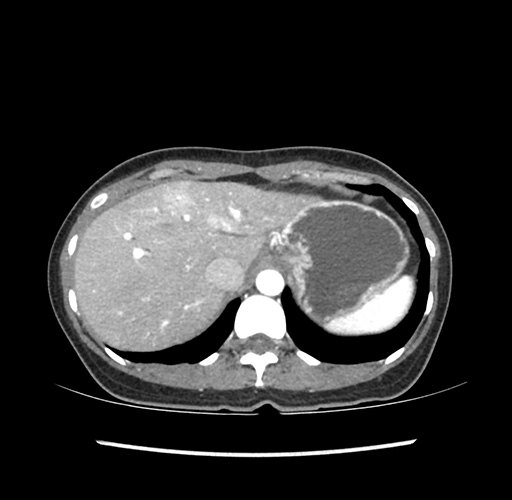

Imaging Analysis

Look through the patient's CT scan to identify any areas of concern for the necessary procedure.

Based on your CT findings, which issue(s) would give reason for "planned slowing down moment(s)" in this case?

Considering a standard left lateral sectionectomy procedure, what step(s) of the operation would you do differently in this case ?